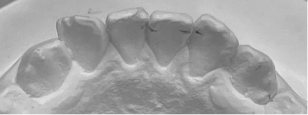

2):当院の矯正の調査法(世界的権威リトル教授の調査方法)

観察方法はPARスコアではなく、もう少しダイレクトな評価になるリトル教授らの方法を使いました。つまり右図のように、後戻りが一番現れやすいと言われている下の前歯において、歯と歯の接触点間の距離をmm単位でデジタル写真上で計測し、それらの合計のミリ数を「指数」とするものです。歯並びが綺麗であれば“0”に近い数字になり、数字が大きいと悪い歯並びを意味します。この写真の歯と歯の接触点間の距離の合計は9.3mmでしたから、指数は9.3になります。